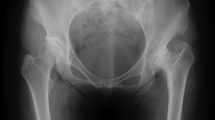

Fourteen paired fresh-frozen (− 20°C) human cadaveric lower legs from four male and three female donors aged 81 years on average (range 59–91 years) with no visible preexisting pathology, trauma or surgery were used. After completion of the entire study, the integrity of ligamentous structures (syndesmotic ligaments) was surgically confirmed under visual control. The specimens were defrosted 24 h before preparation, then cut and embedded at the level of the middle tibia below the tuberosity in polymethylmethacrylate (PMMA; SCS-Beracryl, Suter-Kunststoffe AG, Fraubrunnen, Switzerland) with intact syndesmotic ligaments and membrana interossei. The fibula was cut at the level of embedding to be excluded from fixation. Each specimen was mounted horizontally in an air pressure-controlled radiolucent frame, specifically designed for positioning and axial loading of human cadaveric lower legs during computed tomography (CT) scanning (Fig. 1) 34.

Custom-made loading frame with an artificial lower leg mounted for CT scanning under weightbearing in neutral foot position. The distal end of the frame is made out of radiolucent composite material, the main part is made out of aluminum. A pneumatic cylinder is connected to a compressed air system at the proximal end of the frame.